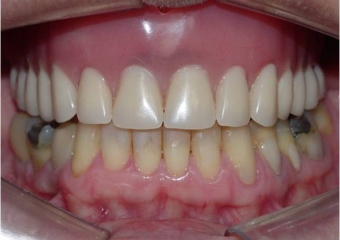

Imagem inicial

Prótese fixa superior em porcelana